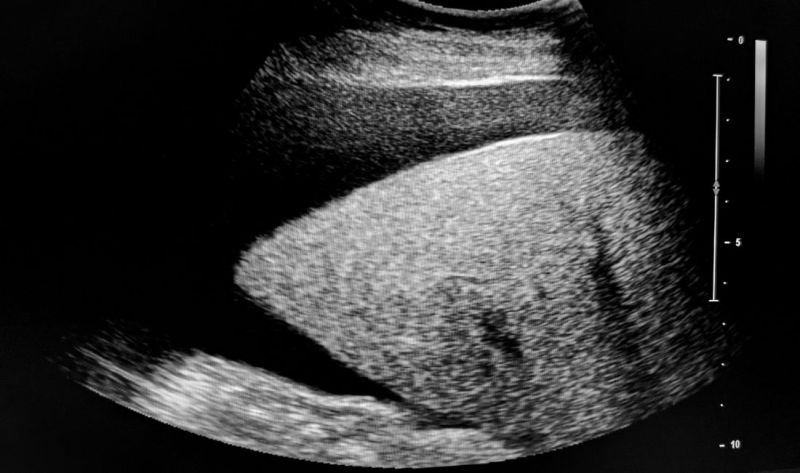

• Rendgen, ultrazvuk, skener, magnetna rezonanca, snimanjem se detaljnije prikazuje unutrašnjost abdomena i omogućava lekaru da lakše pronađe uzrok pojave ascitesa.